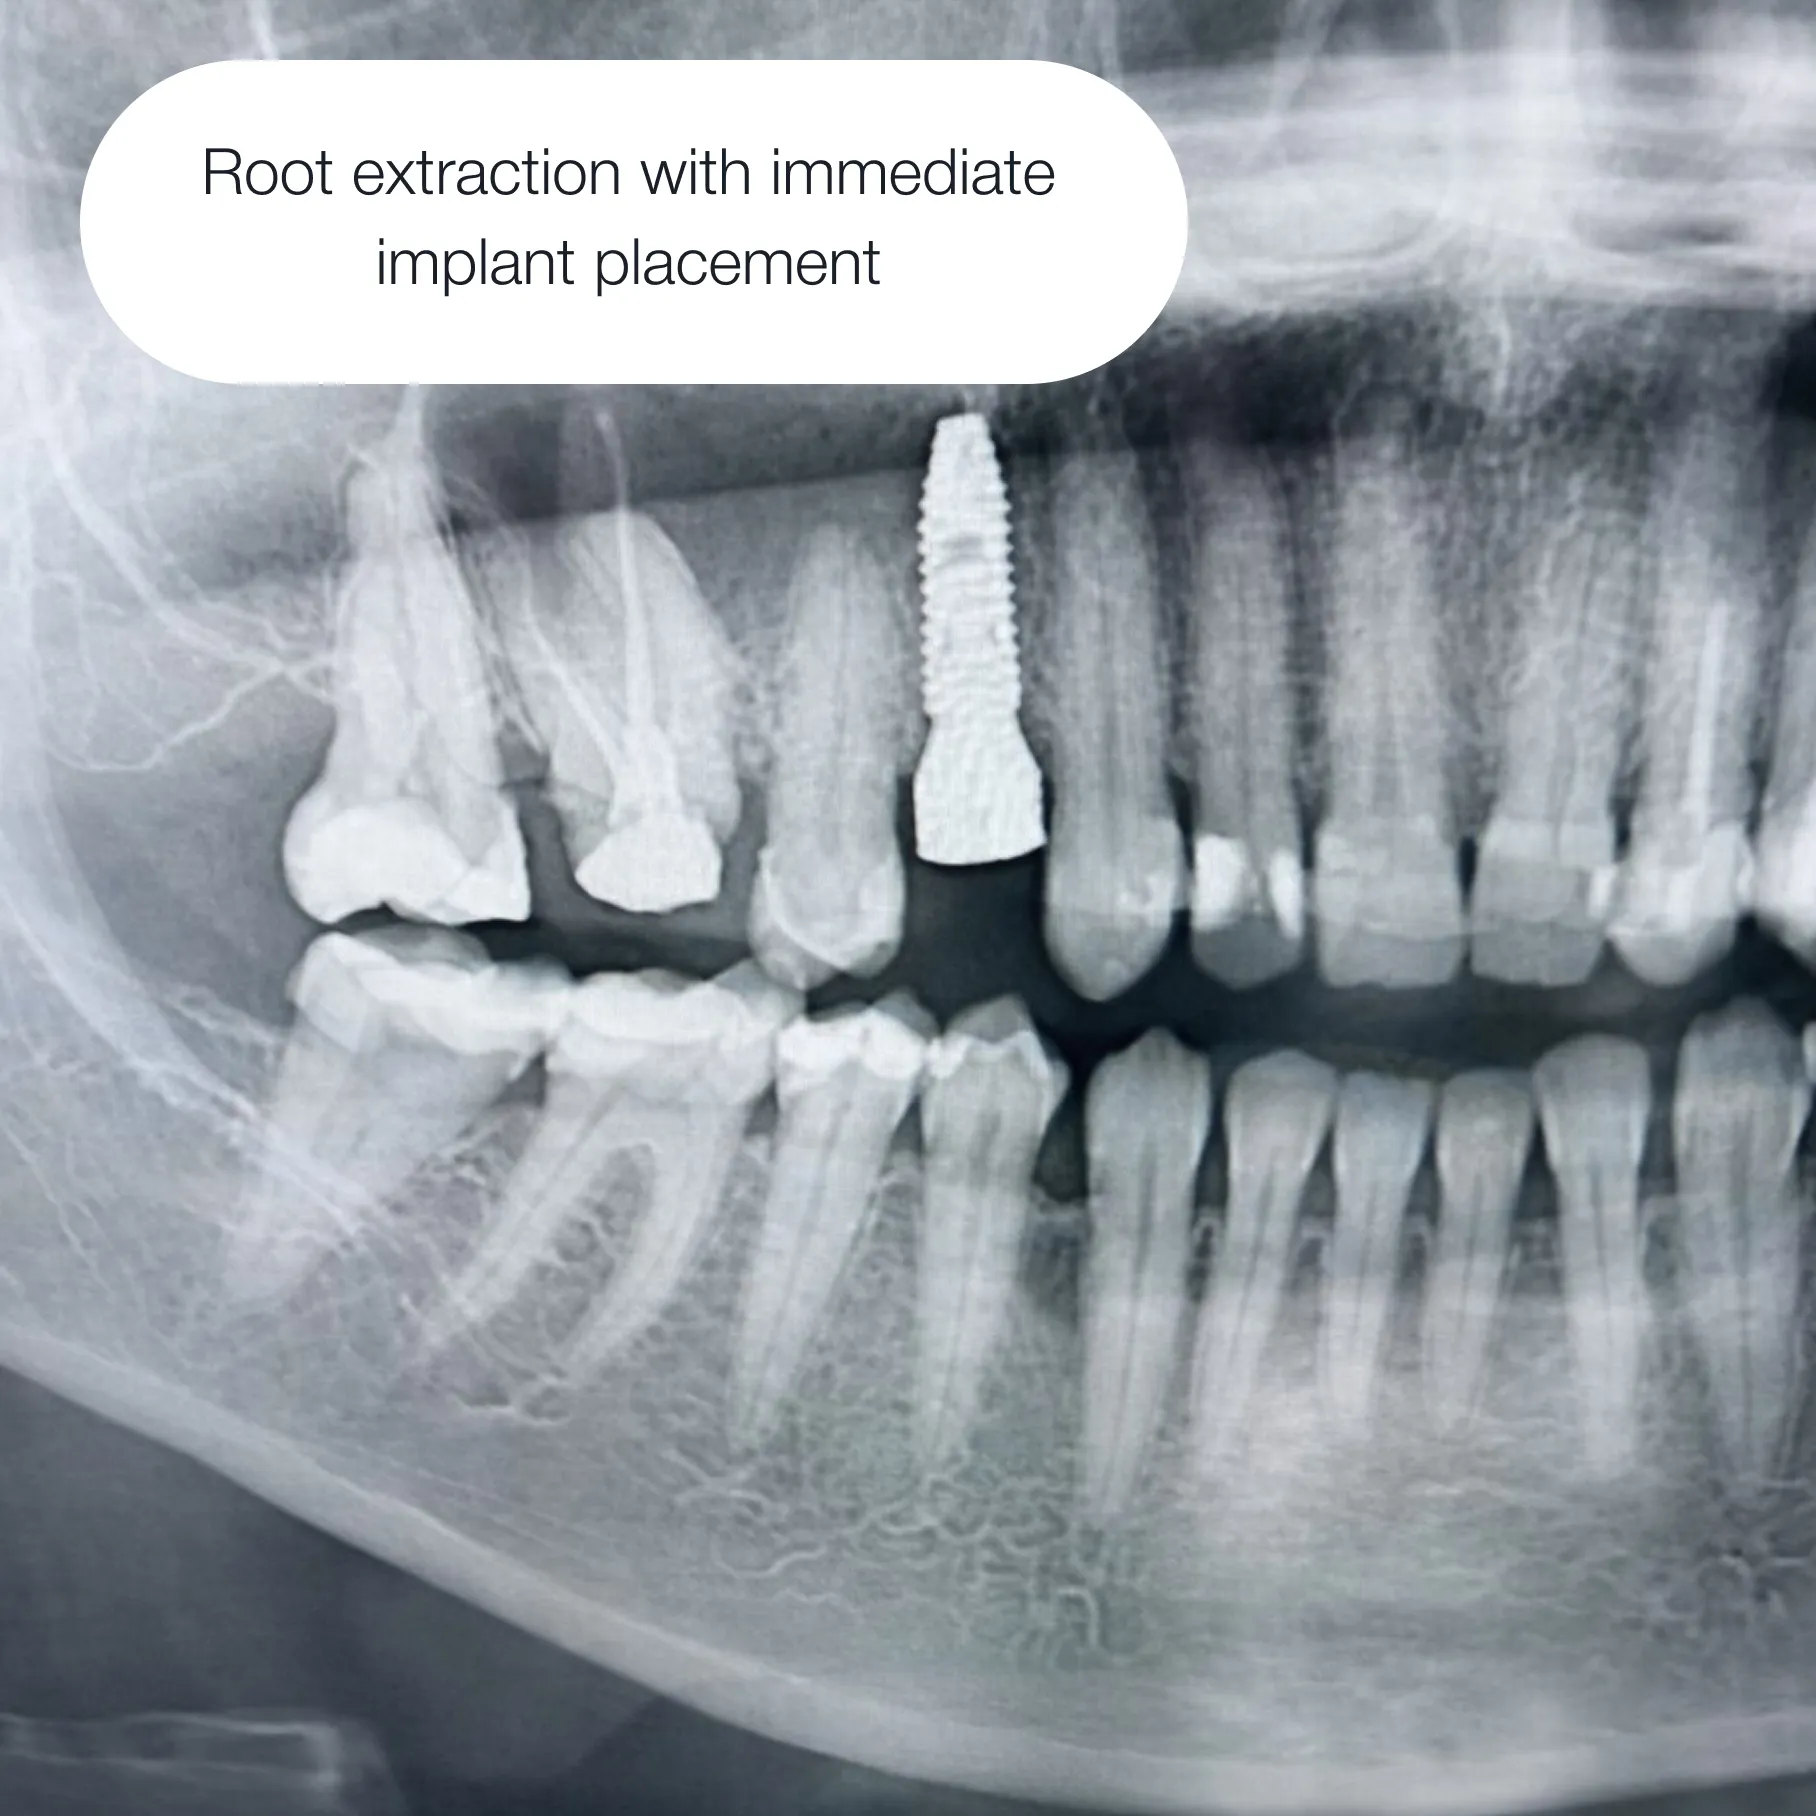

On the day of surgery, the implant is placed and the gum tissue is sutured closed. After the healing period, the second surgical stage follows — the implant is uncovered and a healing abutment is placed to shape the gum.